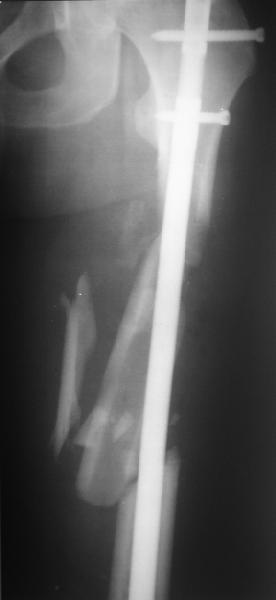

Мы бы не стали открывать, такие переломы срастаются, хотя бы и с

краевым дефектом. То есть если и удалять стержень потом, то сильно

попозже обычного. В приложении пример. Сразу после операции и через 11

мес. Понятное дело, пациент к тому времени давно и не хромал, и функция

колена была полная.